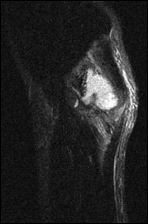

geinjecteerd. Naderhand was er geleidelijk onder de spuitplek een gezwel ontstaan. Het was nu duidelijk zichtbaar en bovendien pijnlijk. [Hiernaast zie je een MRT van het gezwel in een zij-aanzicht - red.] De bodybuilder zweeg erover. Hij was bang dat hij de politie op zijn dak zou krijgen als hij erover sprak. Tegenover de artsen noemde de bodybuilder zijn anaboleninjecties pas nadat ze hem hadden uitgelegd wat 'beroepsgeheim' precies betekent.